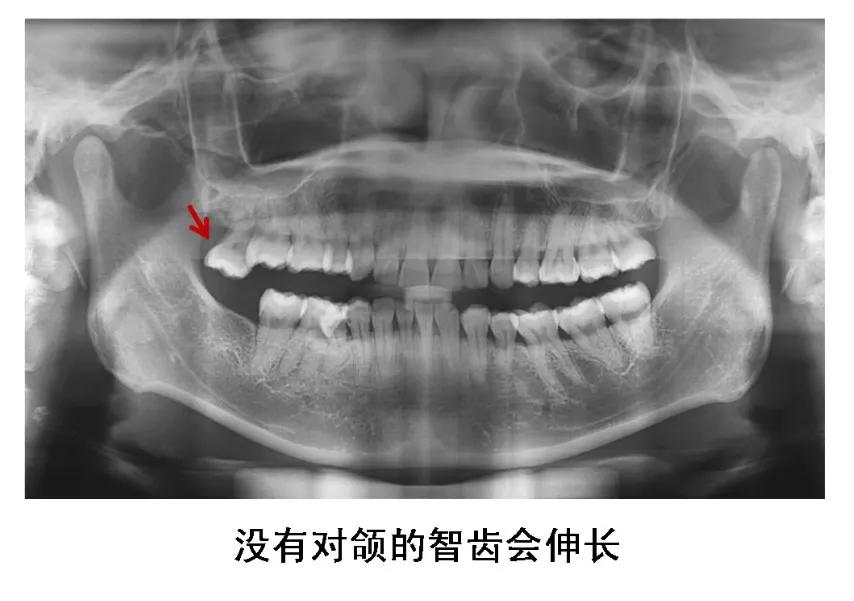

5、没有对颌牙的智齿

这种智齿不能与对颌牙齿建立正常咬合关系,长时间可导致颞下颌关节弹响、张口疼痛、夜磨牙等。没有对颌牙的智齿还会伸长,智齿和邻牙间容易食物嵌塞,并导致邻接面龋。